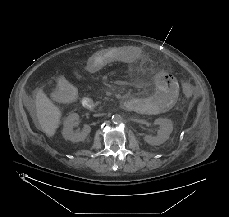

His multiple comorbidities made him a poor surgical candidate, and conservative management with the addition of metronidazole was initiated on hospital day four. Although he showed initial improvement, his abdominal symptoms progressively worsened. He had a heme-positive bowel movement on hospital day 14 with stool culture negative for Clostridium difficile and Norovirus; planned additional studies were not performed due to insufficient material. Repeat abdominal CT on hospital day 15 showed progression of the abdominal process (Fig. 1). The next day he had blood per NG tube, left upper quadrant ecchymosis, increased abdominal distension, and an underlying palpable mass. He continued to decompensate until hospital day 18 when he died after unsuccessful resuscitative efforts for bradycardia, acute hypotension, and acidosis.

Autopsy revealed a large, complex pseudocavitary lesion formed by necrotic omentum encasing several necrotic loops of small bowel with partial entrapment of the transverse colon and two large necrotic abscess cavities in the mesentery and below the stomach. A definite perforation was not identified by gross examination. A large annular, hemorrhagic, necrotic lesion corresponded to the superficial ecchymosis on the left upper to mid quadrant abdominal skin (Fig. 2). Microscopic examination of involved tissues revealed extensive infiltration by PAS-positive, GMS-negative fungal organisms with prominent angiotropism. Some fungal forms showed Zygomycetes morphology with aseptate, ribbon-like hyphae of variable width (Fig. 3). However, some hyphae showed features not typically associated with Zygomycetes, including septa formation, narrower hyphae, and 45-degree angle branching (Fig. 3). Postmortem viral, bacterial, and fungal cultures from the omentum, brain, spleen, liver, kidney, right and left lungs, peripancreatic necrosis, and retro-gastric abscess revealed no evidence of disseminated fungal infection; however, the lungs, omentum, kidney, liver, and brain grew Enterococcus species. Extensive sampling of the tissues showed no lymphoma.